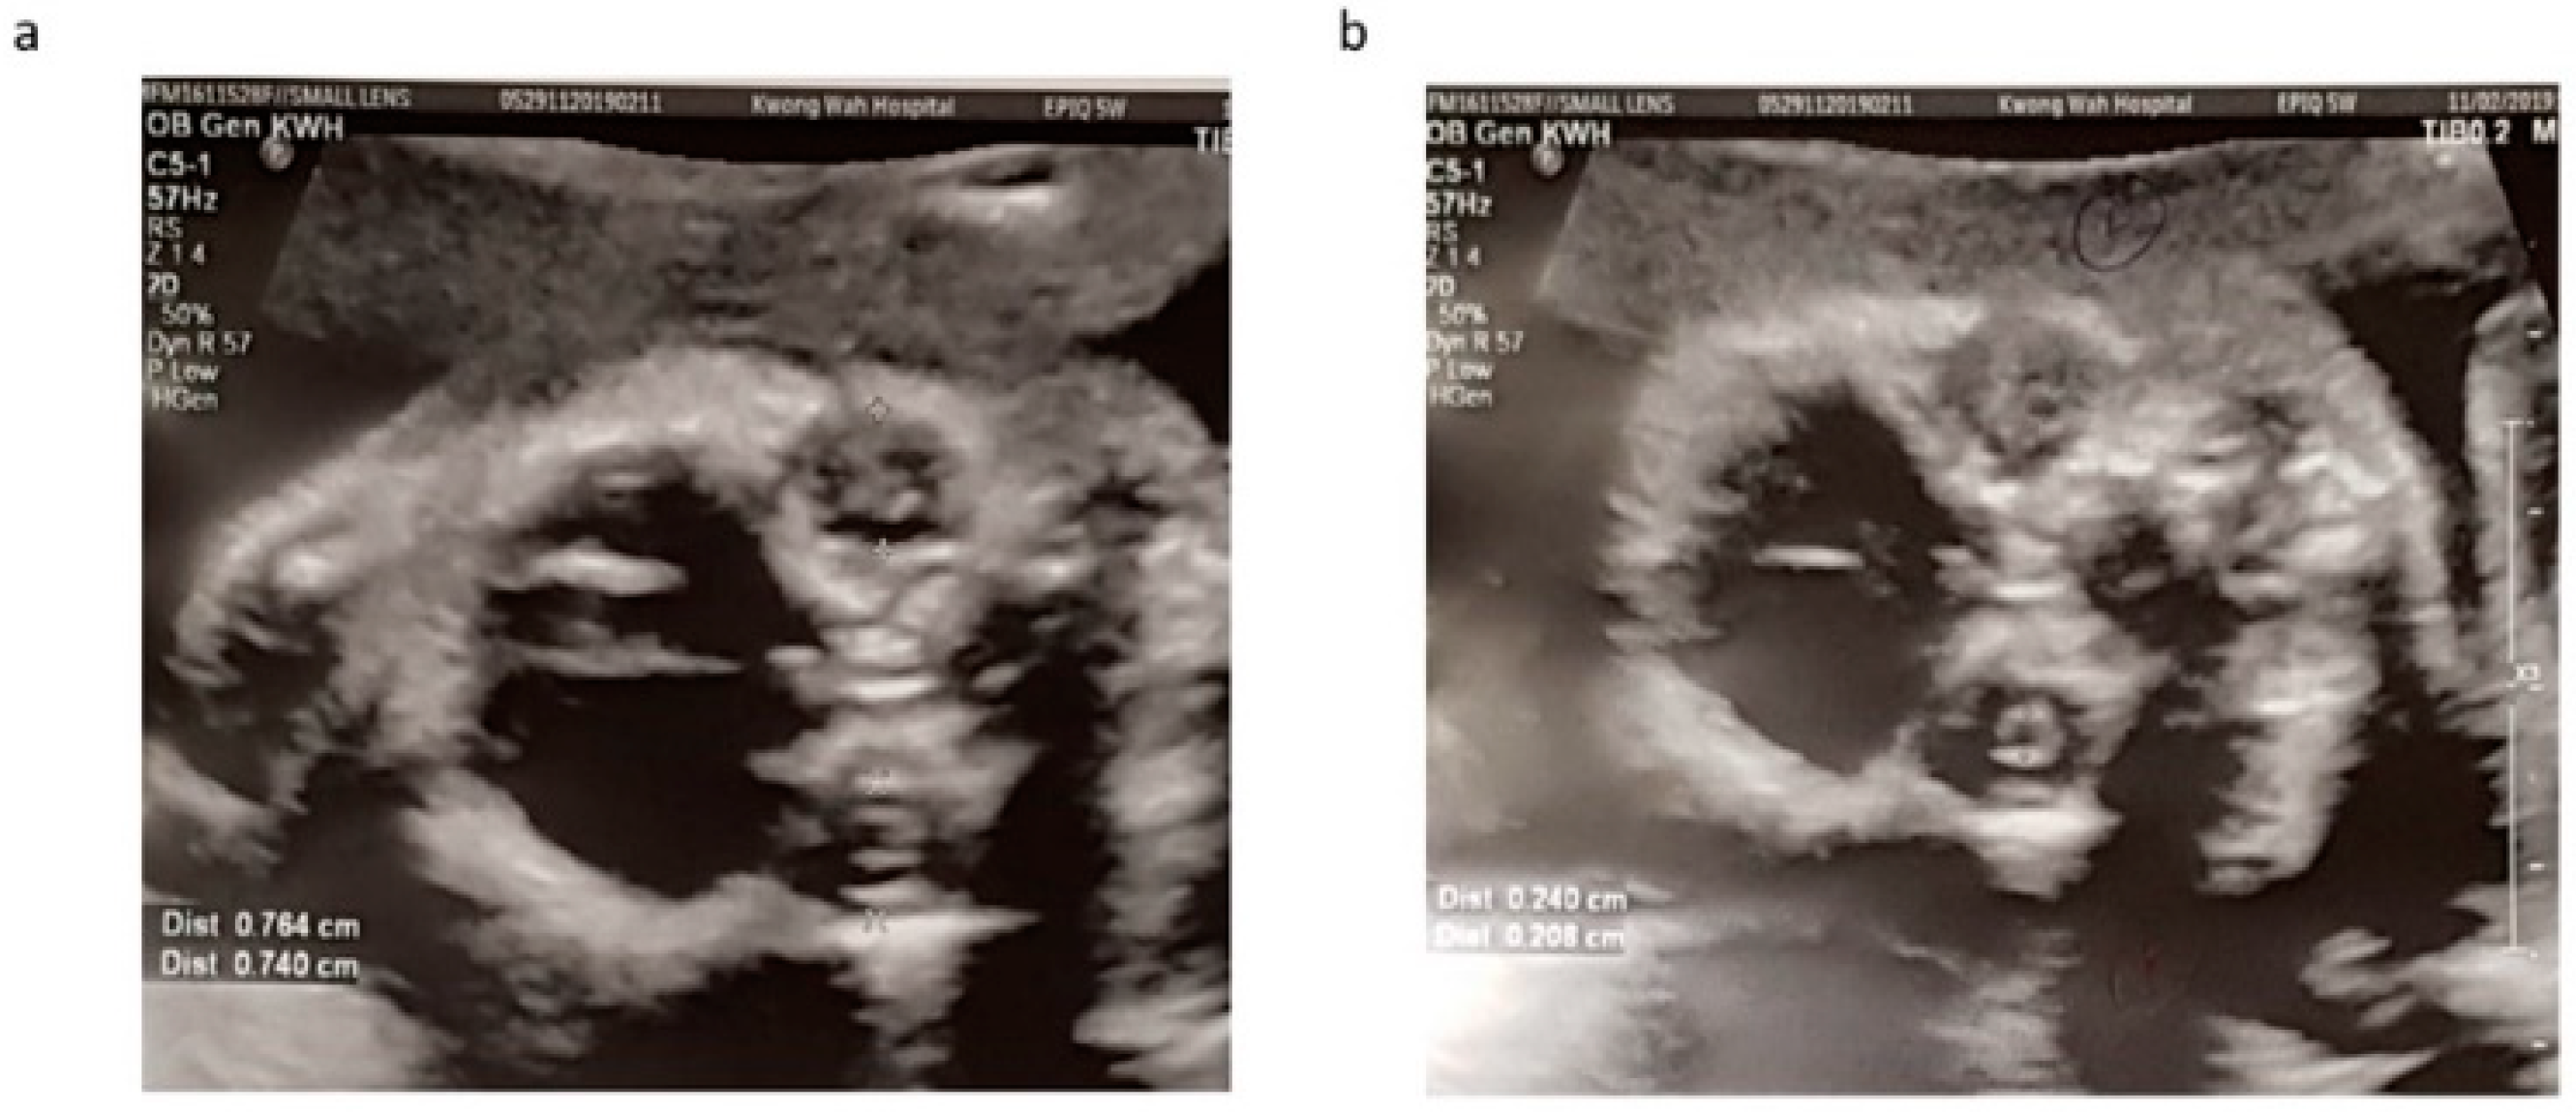

2. Case Report